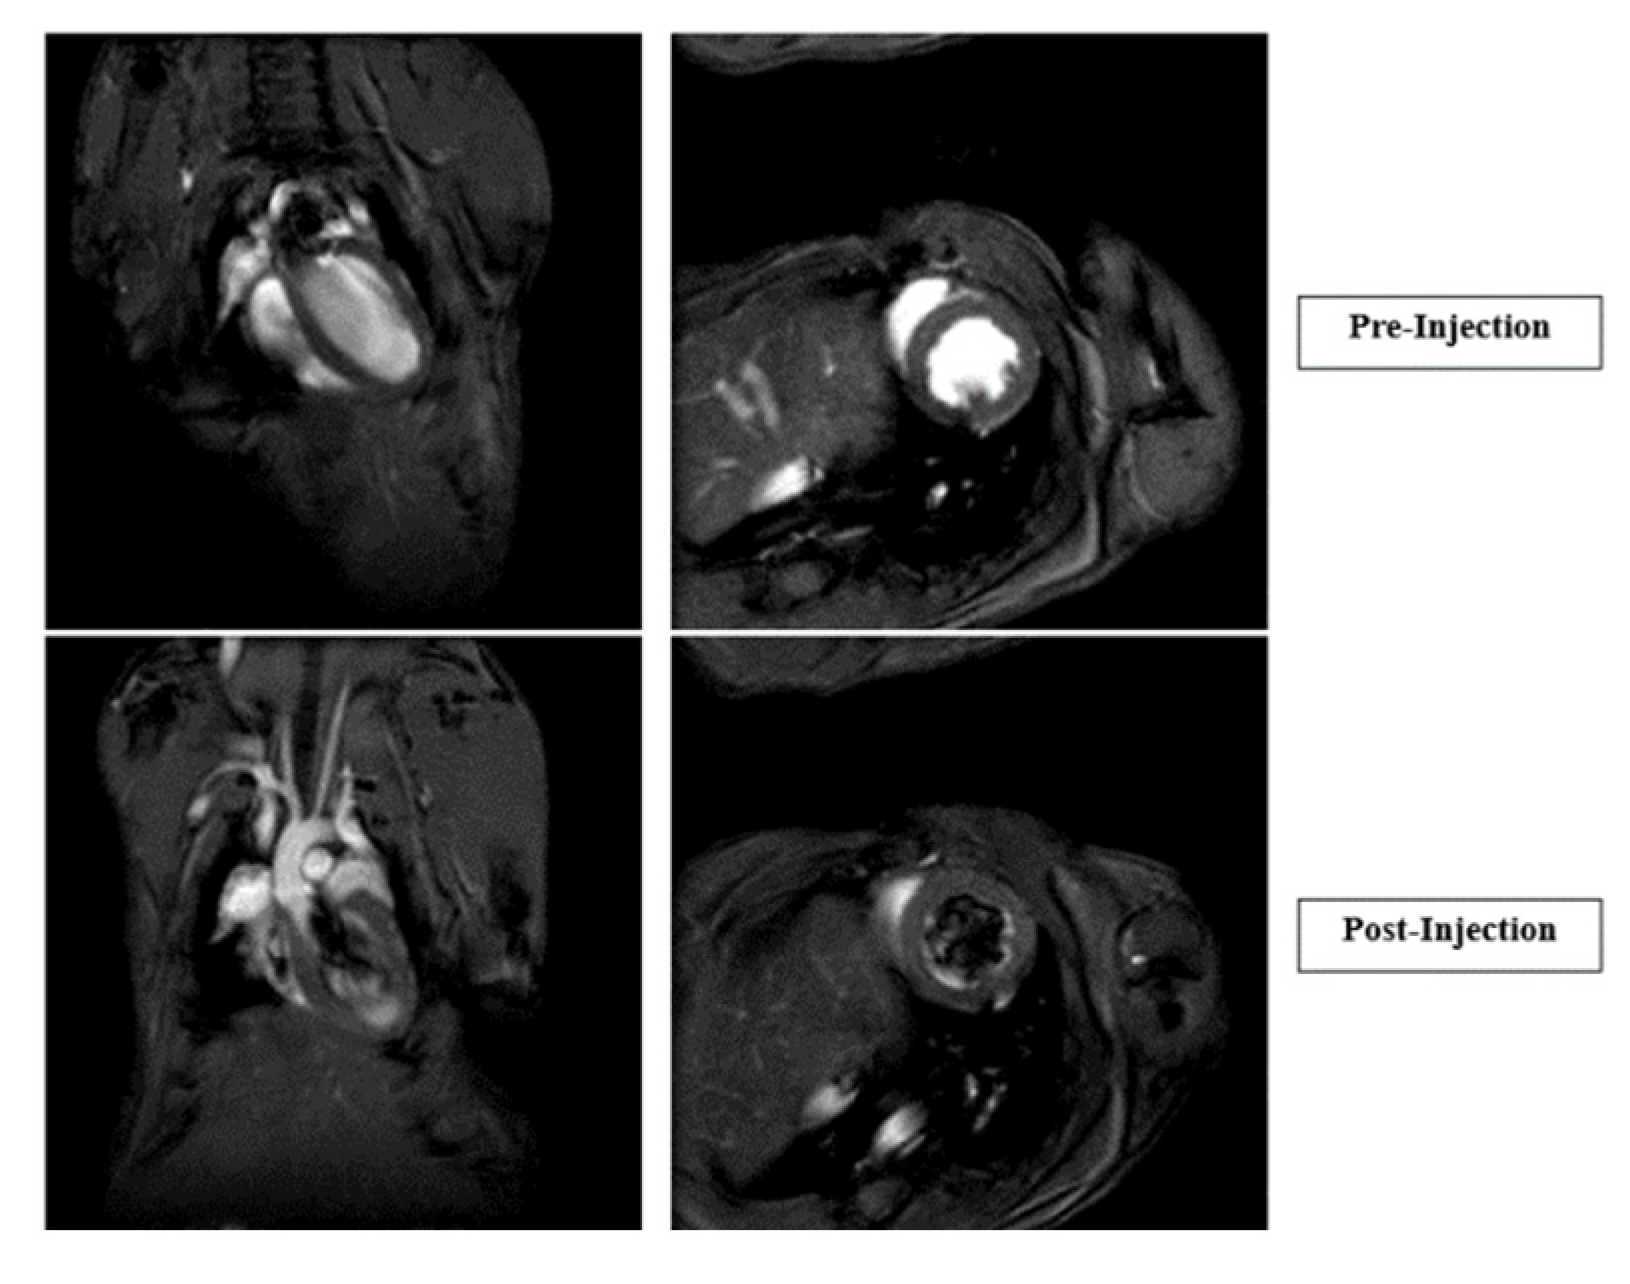

- Zahid, M.; Feldman, K.S.; Garcia-Borrero, G.; Feinstein, T.N.; Pogodzinski, N.; Xu, X.; Yurko, R.; Czachowski, M.; Wu, Y.L.; Mason, N.S.; et al. Cardiac Targeting Peptide, a Novel Cardiac Vector: Studies in Bio-Distribution, Imaging Application, and Mechanism of Transduction. Biomolecules 2018, 8, 147. [Google Scholar] [CrossRef] [PubMed]